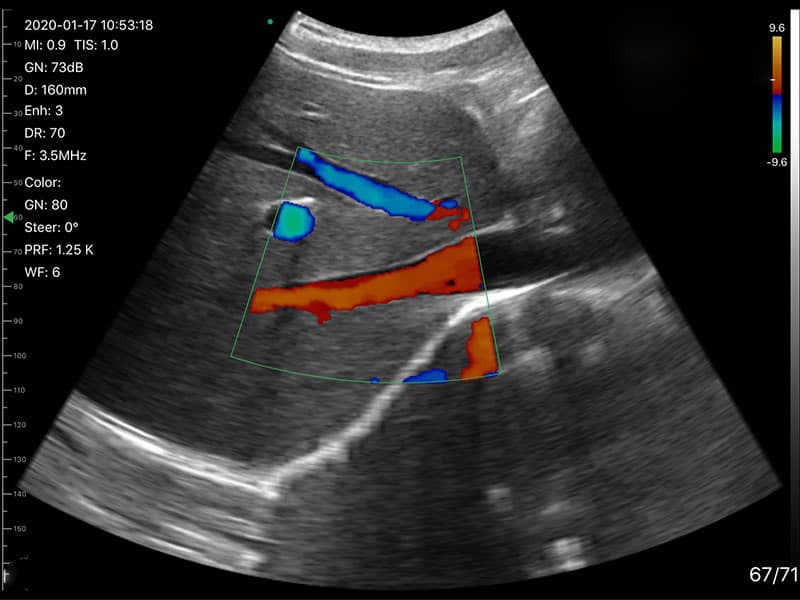

Dr. Roman Bencomo Jenkins, an emergency physician in Atlanta, Georgia, evaluated a nonverbal patient presenting with acute dyspnea. The patient had a medical history significant for chronic heart failure (EF 20-25%), COPD, and a recent ischemic stroke resulting in expressive aphasia. EMS reported that the patient, unable to communicate verbally, appeared distressed and pointed to her chest. Initial oxygen therapy via nasal cannula improved her mild hypoxia.

Upon arrival at the ER, Dr. Jenkins utilized the DRSONO Tri-Scan Max to perform a bedside ultrasound to quickly assess the underlying cause of dyspnea. The findings were:

Dr. Roman Bencomo, an emergency physician in Atlanta, Georgia, evaluated a nonverbal patient presenting with acute dyspnea. The patient had a medical history significant for chronic heart failure (EF 20-25%), COPD, and a recent ischemic stroke resulting in expressive aphasia. EMS reported that the patient, unable to communicate verbally, appeared distressed and pointed to her chest. Initial oxygen therapy via nasal cannula improved her mild hypoxia.

Upon arrival at the ED, Dr. Jenkins utilized the DRSONO Tri-Scan Max to perform a bedside ultrasound to quickly assess the underlying cause of dyspnea.

Lung Ultrasound Findings:

The lung ultrasound revealed no B-lines or signs of pulmonary edema, ruling out acute CHF exacerbation as the cause of dyspnea.

Cardiac Ultrasound Findings: The apical 4-chamber view demonstrated normal RV size and function. No evidence of acute right heart strain or pulmonary embolism (PE) was identified.